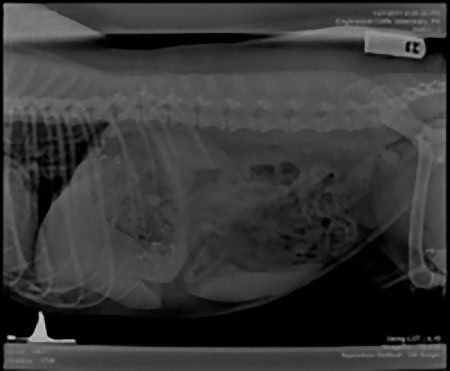

この画像を大きなサイズで見る準優勝写真:

12歳のビークル犬の体内に宿る、靴ひも、腐葉土、ストッキング、プラスチック、ネクタイと車用ブラシなど。

この画像を大きなサイズで見る